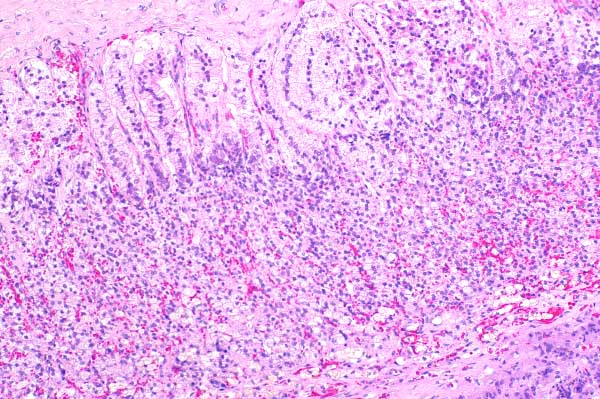

10x   |   Hematoxylin and Eosin

The zona fasciculata and zona reticularis are severely atrophied.